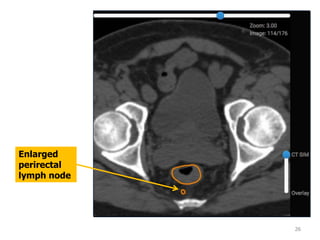

Differentiating a lymph node from a vessel

1. Use MRI overlay

2. Scroll up and down: nodes will be rounded

structures that disappear then reappear

3. Contour the vessels before contouring the GTV

4. Sub-centimeter perirectal nodes are contoured in

the GTV to show you they are in the standard CTV.

These DO NOT need to be contoured unless grossly

enlarged.

25

26

Enlarged

perirectal

lymph node